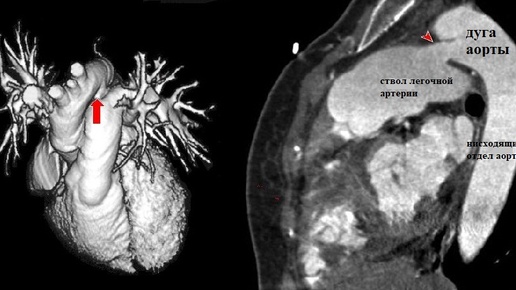

Открытый артериальный проток (ОАП), также называемый Боталловым, относится к врожденным порокам сердца – это аномальное сообщение между лёгочной артерией и аортой. В норме он служит для кровоснабжения плода (эмбриона) в утробе женщины и должен в течение нескольких недель (до 2-х месяцев) после рождения закрыться. Однако, при развитии этой патологии процесс закрытия (облитерации) артериального протока нарушается. В статье поговорим об опасности состояния, методах диагностики, лечении, профилактике...

Еще один врожденный порок сердца — открытый артериальный проток. Второе название этой патологии — незаращение Боталлова протока. Из сердца выходят две крупные артерии: аорта и легочная артерия. Аорта выходит из левого желудочка, а легочная артерия — из правого. (Прочтите статьи: "Строение сердца человека" и "Как работает сердце?") Важный момент: выходя из сердца, эти артерии расположены очень близко друг к другу. Аорта — это начальный этап большого круга кровообращения. Внутри этого сосуда находится артериальная кровь, насыщенная кислородом...